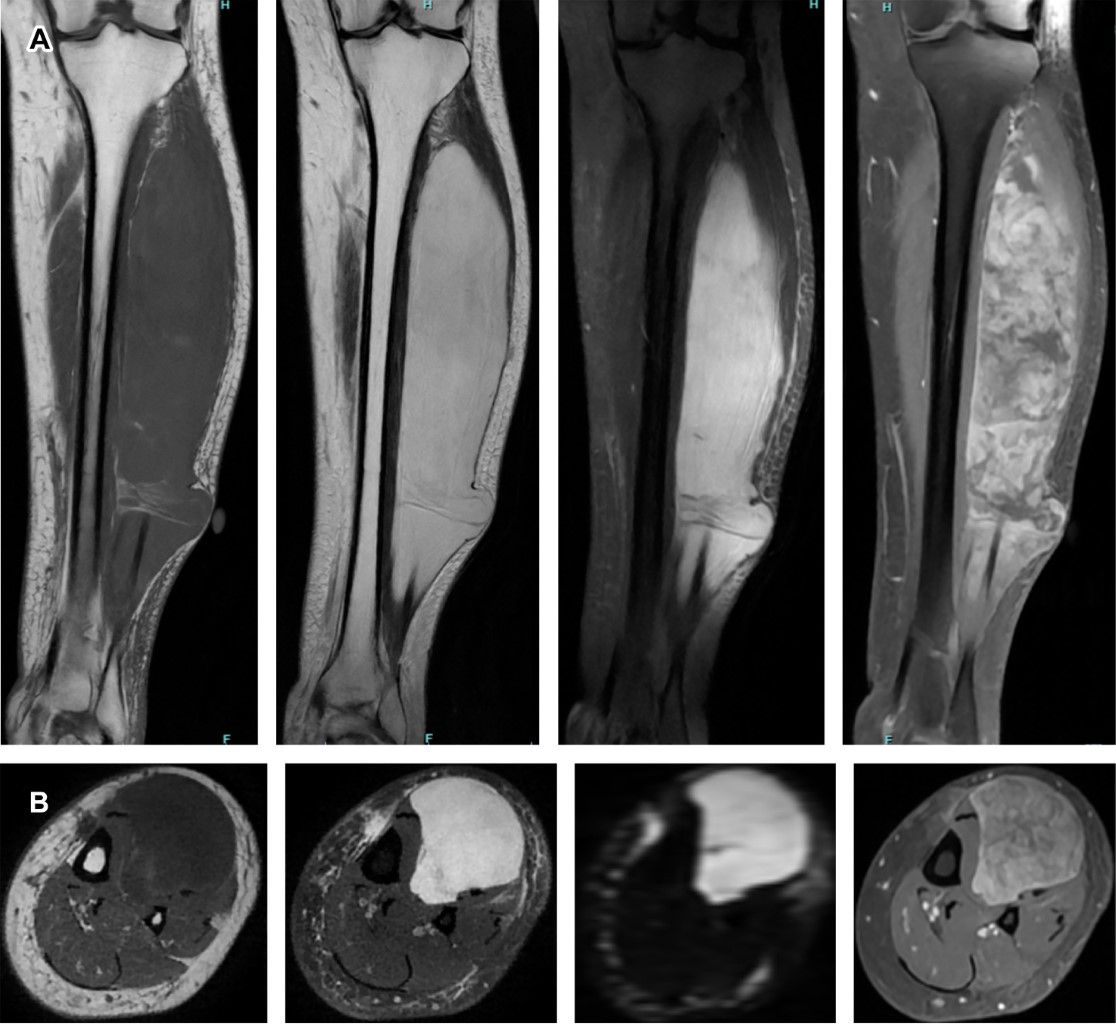

Femenino de 47 años sin antecedentes de importancia, quien presenta tumoración en extremidad inferior izquierda. La RM revela lesión ovoidea en el músculo extensor largo de los dedos y extensor largo del primer dedo, de contenido hiperintenso en secuencia T2 con zona hipointensa central con aparente matriz fibrovascular e importante realce heterogéneo en secuencias ponderadas con medio de contraste altamente sugestivo de fibrosarcoma (Figura 1).

Radiológicamente aparecen como lesiones ovoides, localizadas, con márgenes ligeramente irregulares.1 Suelen localizarse debajo de la fascia profunda y tienden a invadir la superficie, afectando la piel y el tejido subcutáneo. La RM es el estudio de elección para evaluar este tipo de neoplasias, caracterizándose por presentar señal hipointensa en T1, señal heterogénea de baja y alta intensidad en T2 y restricción a la difusión. En la RM contrastada, las lesiones muestran realce periférico heterogéneo o realce con patrón de espiga (altamente sugestivo de un fibrosarcoma adulto).2 La TC evalúa compromiso óseo e identifica áreas en forma de bandas de baja densidad (tabiques fibrosos), signo importante para el diagnóstico correcto de esta entidad.1,2

Figura 1